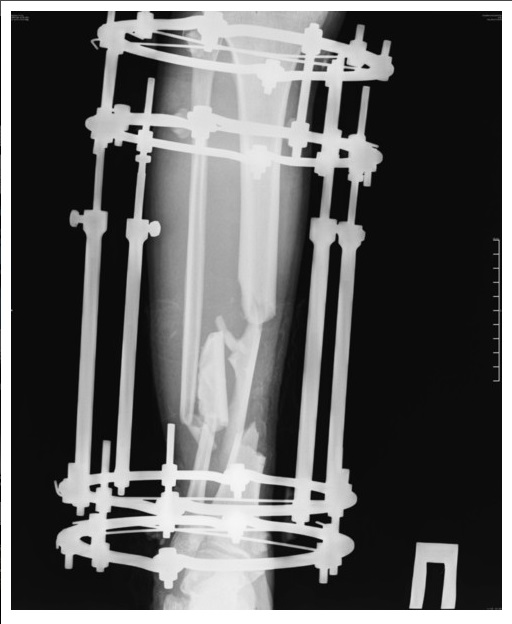

«Было это еще 7 июня, но до сих пор, по прошествии двух операций ему не собрали все кости. Одну кость и вовсе забыли на месте ДТП и теперь вместо нее требуется имплант. На одной ноге у него сейчас 18 переломов и 3 из них гниют, один из кусков кости встал поперёк, врачи опасаются её доставать или разворачивать, ибо можно занести ещё больше инфекции, если делать, то надо делать сразу всё комплексно, а пока приходится постоянно чистить, чтоб не было заражения, никакие обезболивающие уже не помогают, организм уже к ним адаптировался, и приходится терпеть эти боли. Нам же остается только медленно собирать деньги», - сообщают близкие пострадавшего на сайте, созданном в поддержку Валеры.